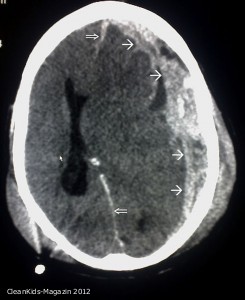

Ausgedehnte Blutung unter der harten Hirnhaut (subdurales Hämatom markiert durch Einzelpfeile) mit Verlegung des rechten Seitenventrikels und Verdrängung des Hirngewebes mit Mittelllinienverlagerung nach links (Doppelpfeile)

Äußerlich hinterlässt eine solche Gewalteinwirkung meist keine Spuren. Die Symptome, die in seiner Folge auftreten, sind für den Laien häufig schwer zuzuordnen: Die Kinder sind schläfrig, geistig abwesend, sie erbrechen und bekommen Krampfanfälle. Die Hirnverletzungen zeigen sich erst in der Bildgebung – bei einer MRT-, Ultraschall-, oder CT- Untersuchung. „Die Schädigungen, die wir dann entdecken, variieren je nach Schwere des Schütteltraumas. Am häufigsten lassen sich Subduralhämatome, also Blutergüsse unter der Hirnhaut, oft mehrfach und dann unterschiedlichen Alters feststellen“, so Seitz. In 60 bis 95 Prozent der Fälle kommt es beim Schütteltrauma außerdem zu Netzhautblutungen, denn durch die beim Schütteln freigesetzten Schleuderkräfte reißen Blutgefäße in den Augen ein. „Die Kombination von sogenannten mehrzeitigen Subduralhämatomen und Netzhautblutungen ist typisch für das Schütteltrauma. Ein solches Verletzungsmuster ist bei Unfällen praktisch ausgeschlossen“, so Seitz. Ein Verdacht auf Misshandlung erhärtet sich, wenn die Bildgebung Misshandlungsspuren der Vergangenheit offenbart: Subduralhämatome sind im MRT-Bild oft mehrere Wochen, andere typische Verletzungsfolgen des Gehirns selbst durch Sauerstoffmangel oder Schwerverletzungen lebenslang sichtbar. Darüber hinaus kann die frühzeitig durchgeführte MRT eine durch Verletzungen hervorgerufene Störung des Sauerstoff-Kohlendioxid-Austausches in den Blutgefäßen feststellen. Eine schnelle Diagnose ist wichtig, um schwere Organschäden oder gar Tod zu verhindern.